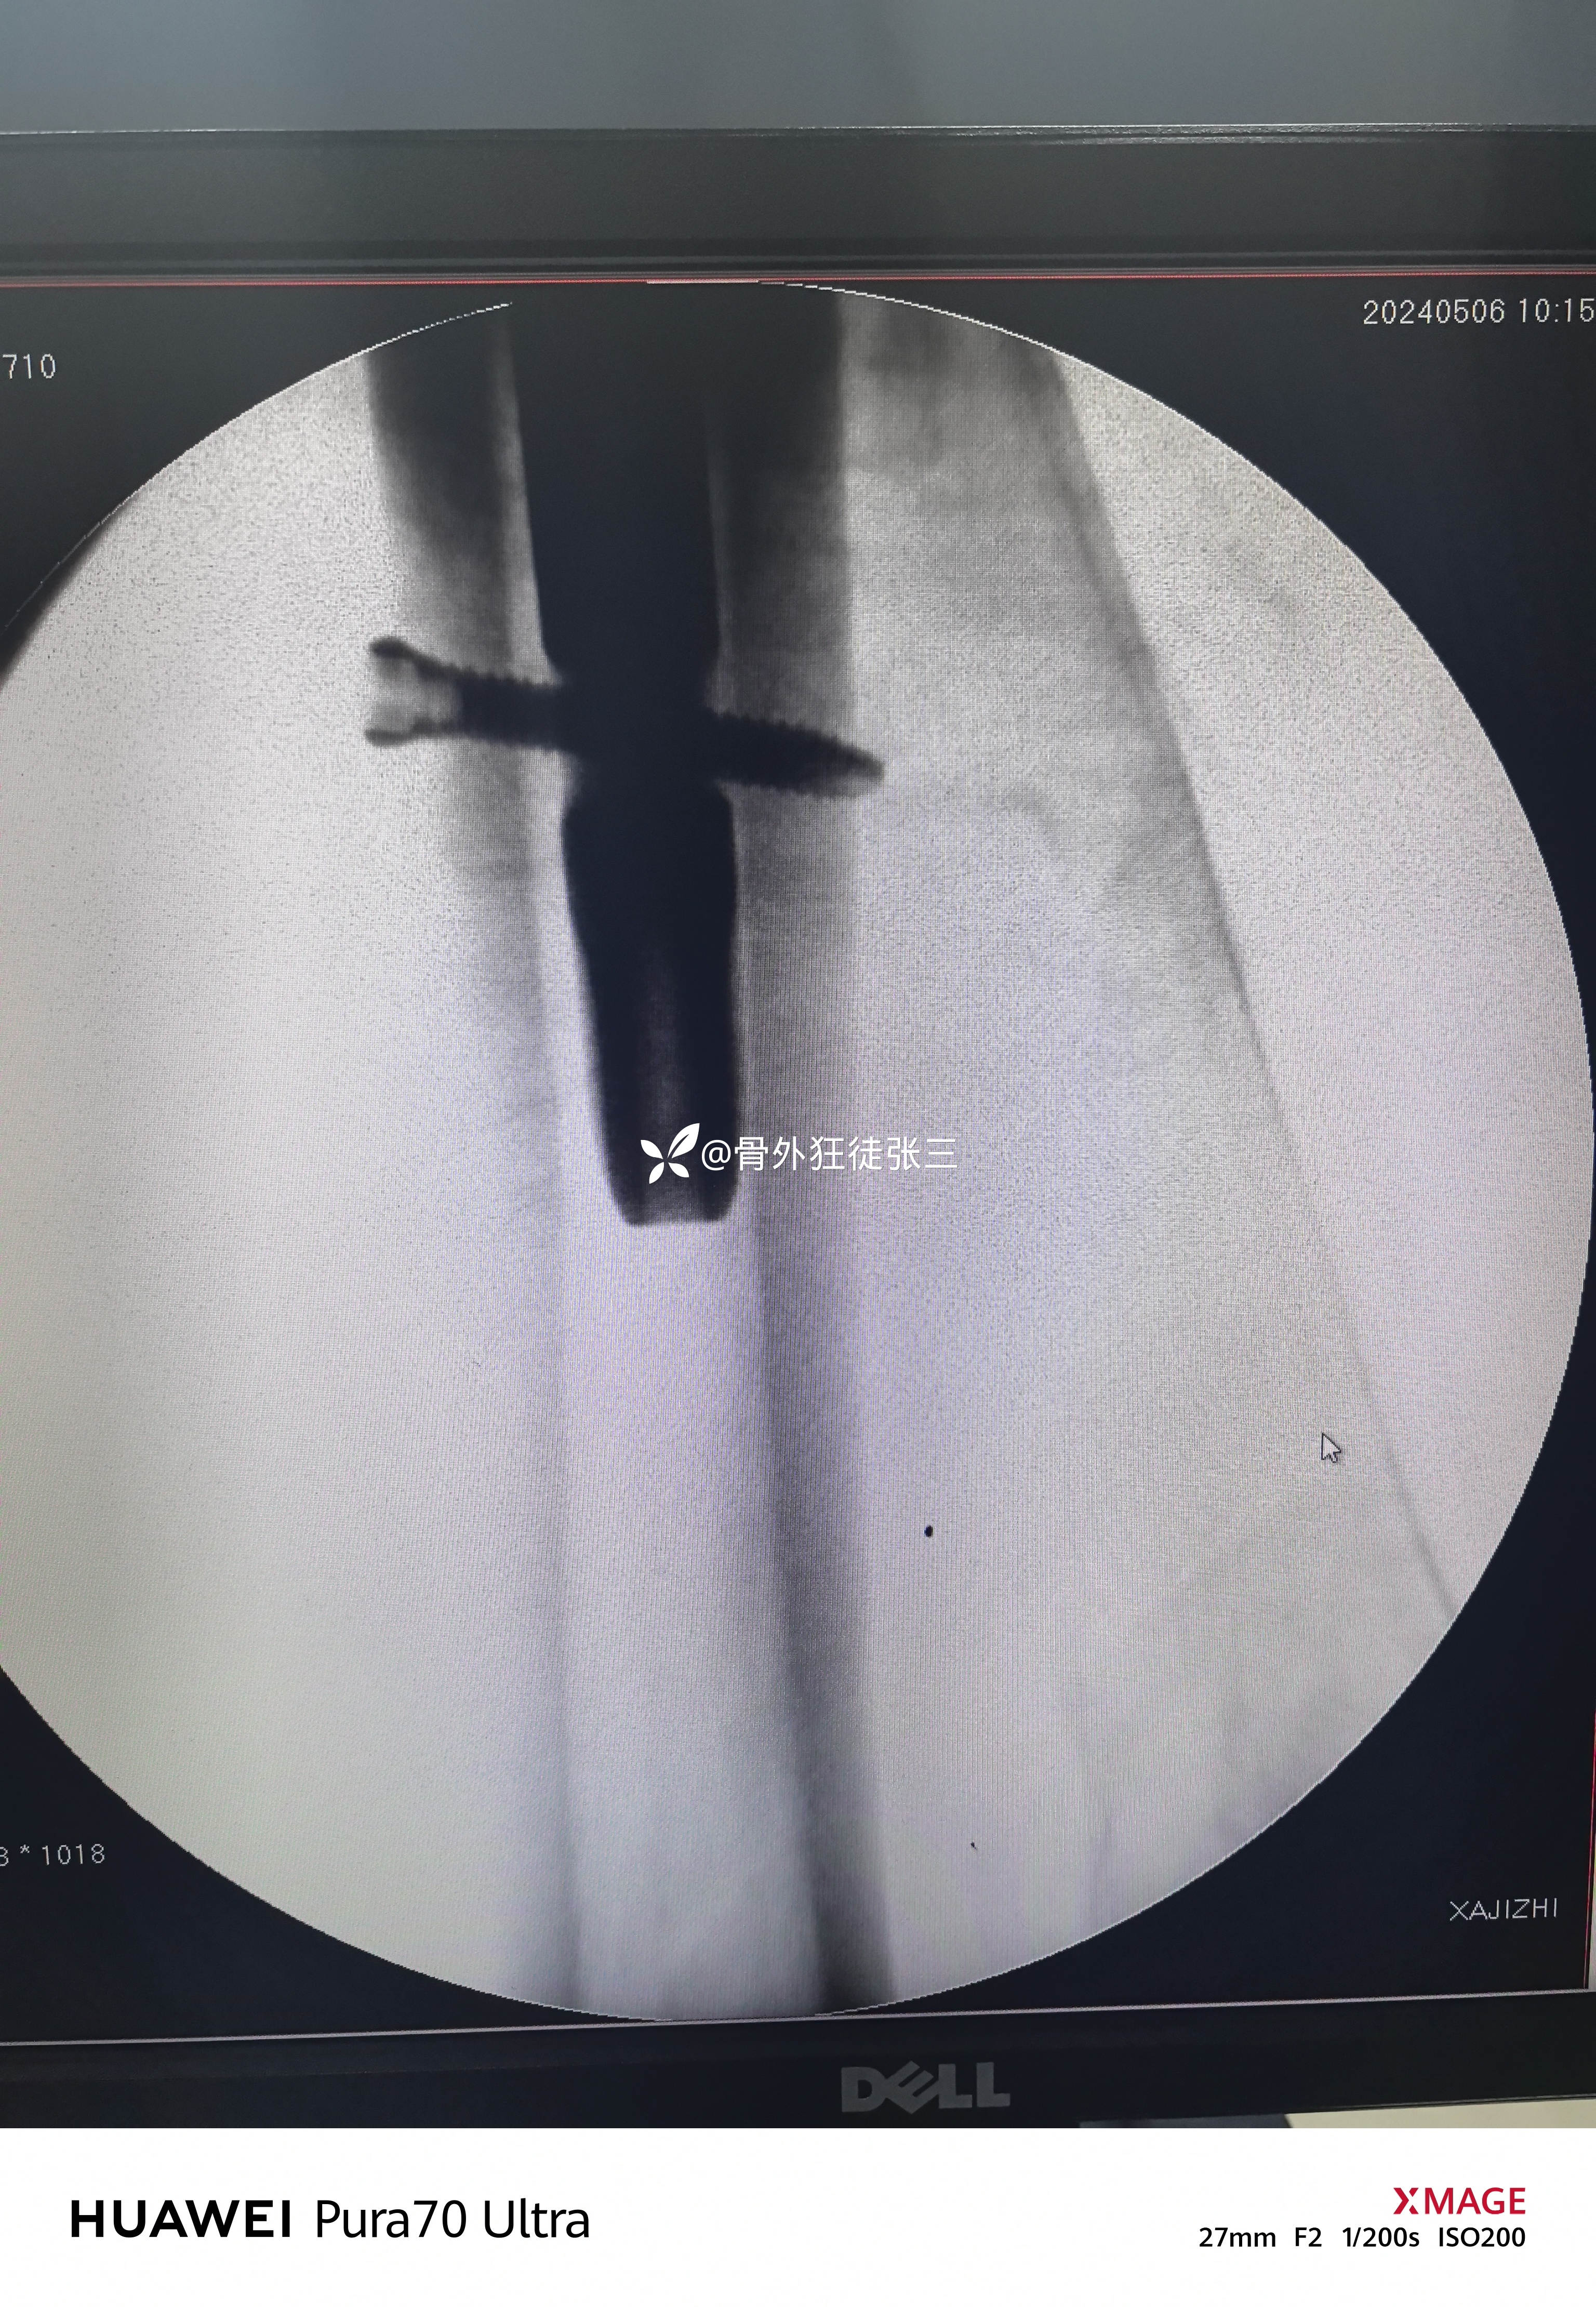

牵开器——透视正侧位——切口——确定进针点——铰刀开口——开口钻开口——金手指——导针置入——直接使用170 mmX12 mm主钉插入——调整前倾主钉深度和前倾——透视正位中下1/3,侧位基本居中——远端锁钉——近端锁尾端尾帽,——再次透视正、侧、蛙位——冲洗、缝合1-1-3 ——09:37-10:16 ——40分钟手术结束,透视16次,每次约一分钟,手术操作20分钟。

术后复查

螺旋刀片还能再长5mm